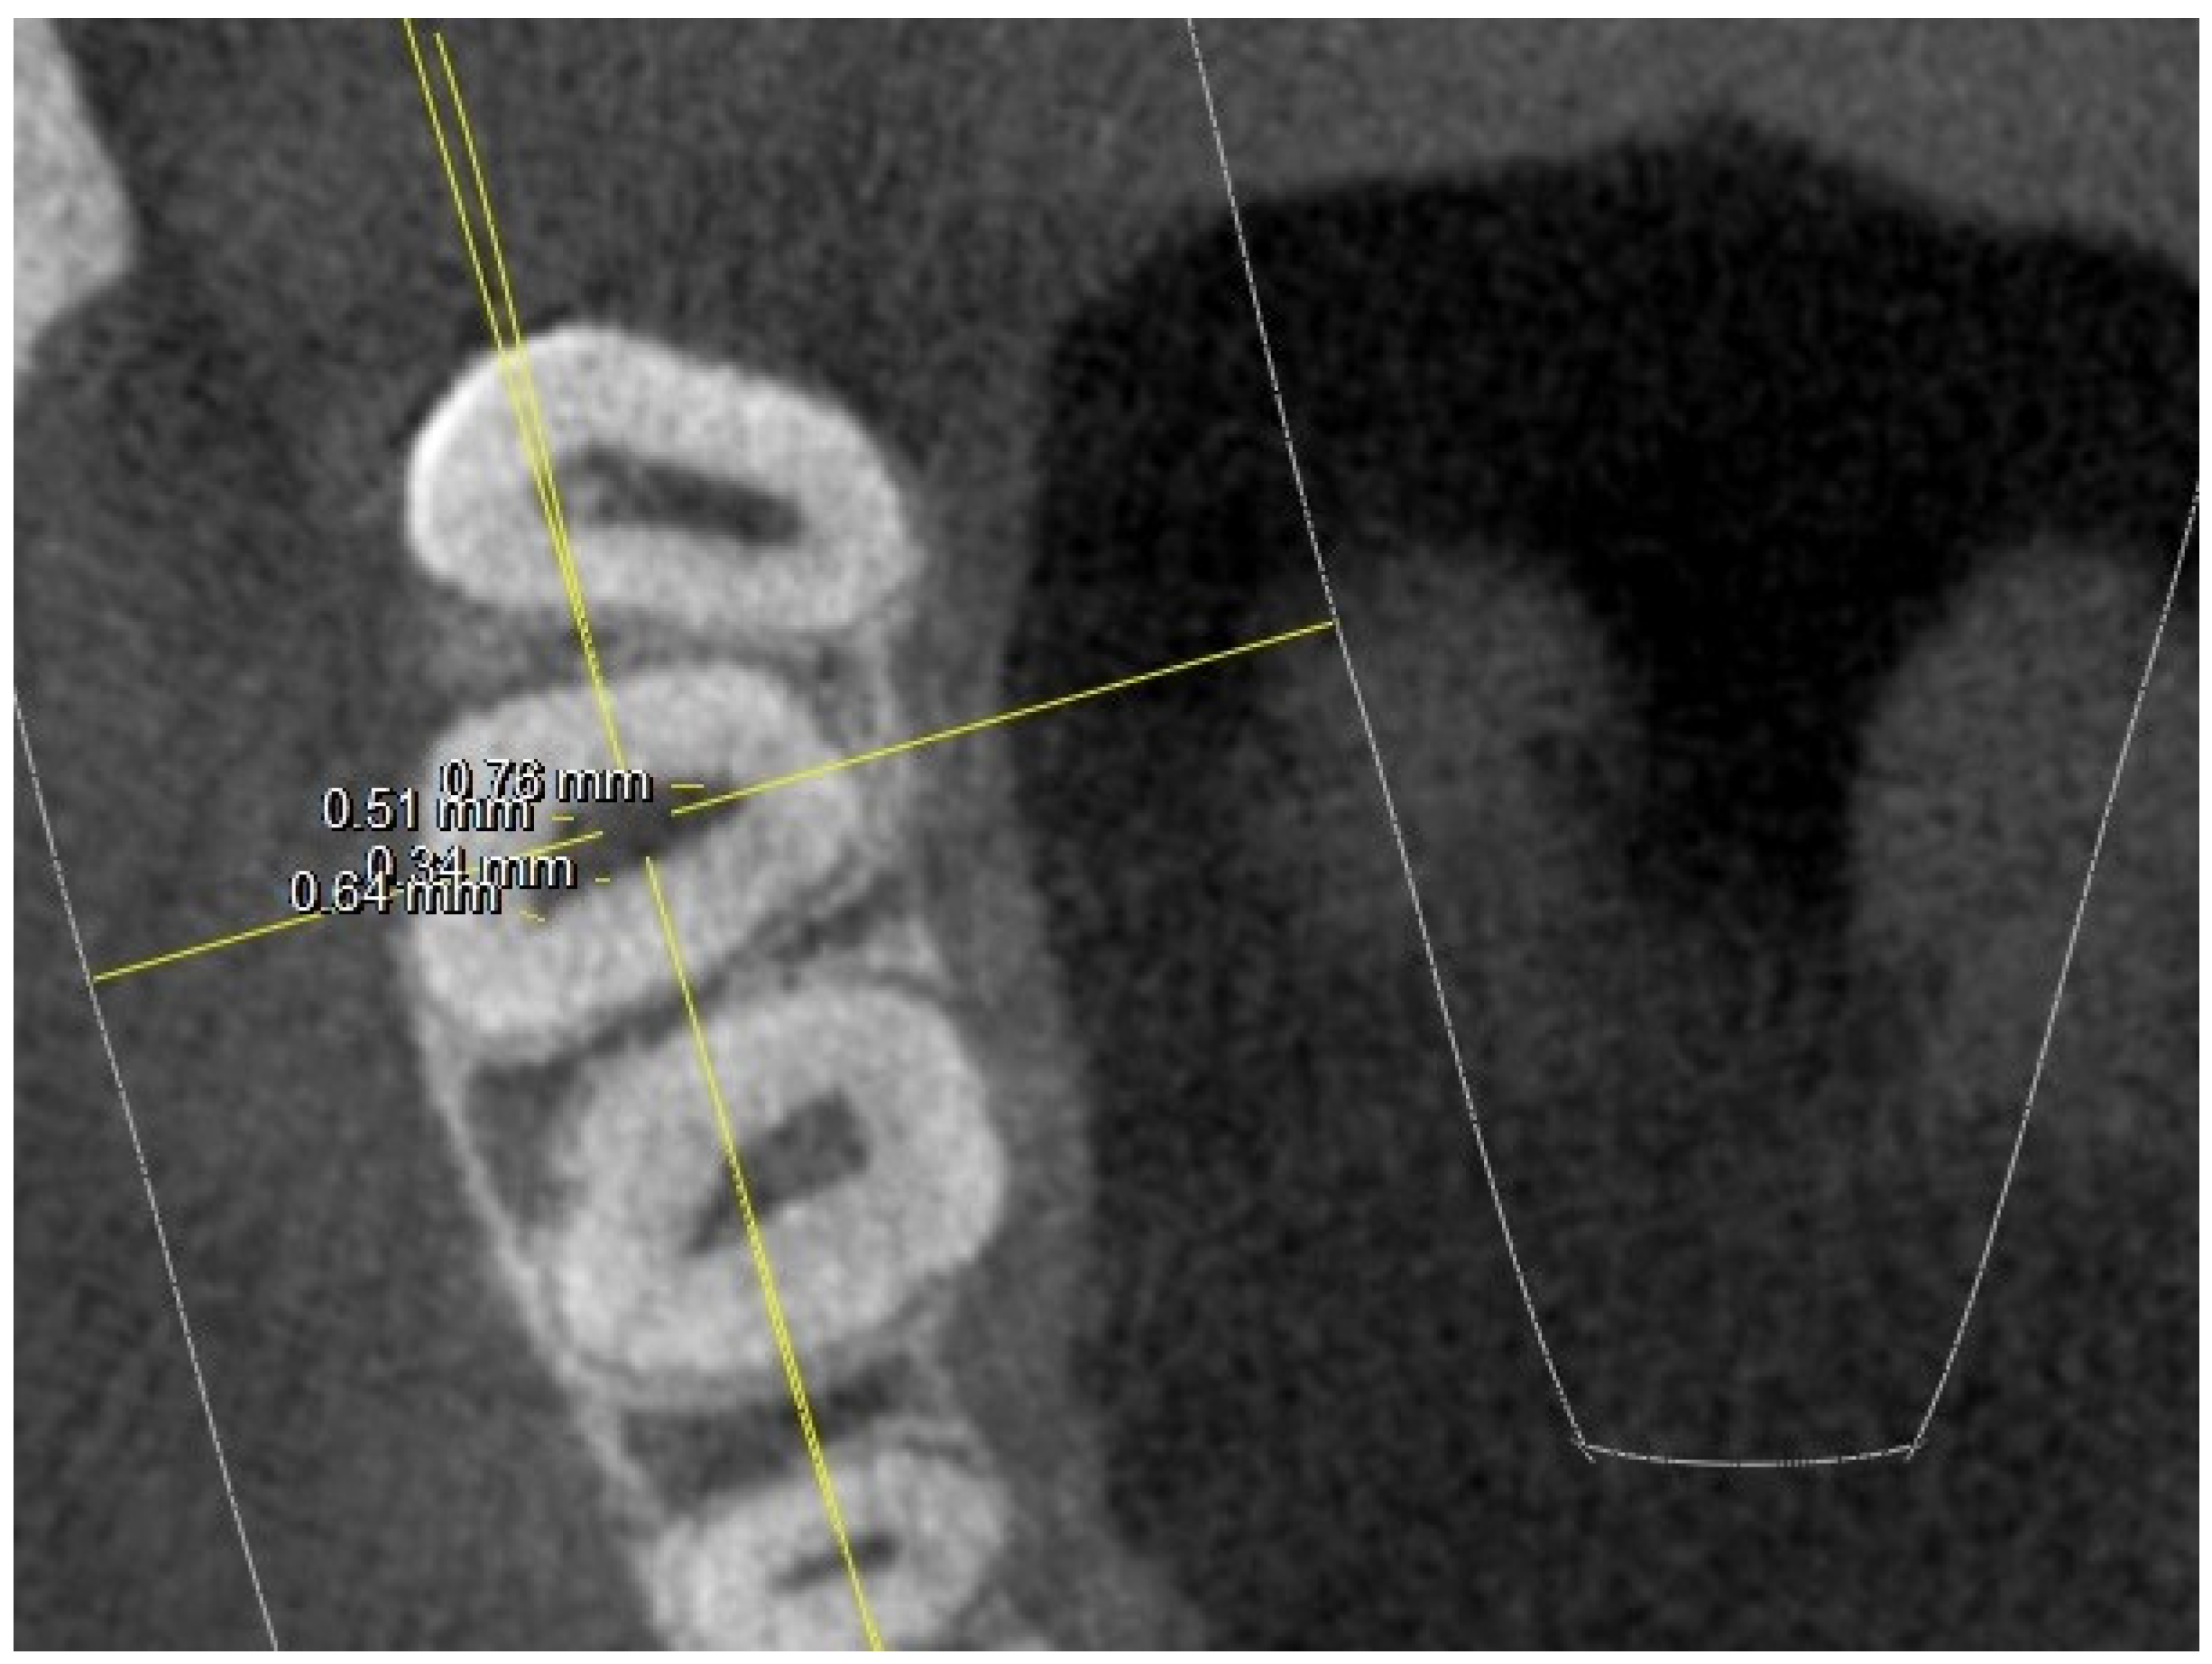

- diameter of root canal orifices;

| At the orifice: M-B diameter | 0.65 | 0.21 | 0.81 | 0.17 | 0.74 | 0.24 | 0.67 | 0.21 | ||

| D-B diameter | 0.69 | 0.11(2 NO) | 0.72 | 0.14 (1 NO) | 0.65 | 0.12 (1 NO) | 0.69 | 0.15 (3 NO) | ||

| Palatal diameter | 0.89 | 0.18 | 0.89 | 0.21 | 1.12 | 0.16 | 0.89 | 0.18 | ||

| Mb2 diameter | 0.38 | 0.12 (6 NO) | 0.3 | 0.8 (10 NO) | 0.39 | 0.9 (3 NO) | 0.34 | 0.8 (15 NO) | ||